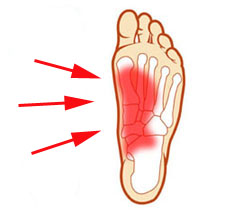

Sprain: When the fibers of the tissue tear due to overstretched ligaments, a sprain occurs, and a sprain is known to cause extreme pain. Muscle Injury: Overloading, overuse, over-stretching, or bruising of the muscles and tendons of the foot may lead to severe pain in the foot. Plantar Fasciitis: Planter fascia strains are generally felt as the pain at the bottom of the foot. This condition is known as plantar fasciitis. Wrong Shoes: Wearing narrow toed shoes may lead to development of a bunion, a big, hard, and painful protrusion at the base of the big toe, causing pain in the foot. Hammer Toes: As contraction of muscles leads to hammer or curled toes, it is often a cause of severe pain.

Sprain: When the fibers of the tissue tear due to overstretched ligaments, a sprain occurs, and a sprain is known to cause extreme pain. Muscle Injury: Overloading, overuse, over-stretching, or bruising of the muscles and tendons of the foot may lead to severe pain in the foot. Plantar Fasciitis: Planter fascia strains are generally felt as the pain at the bottom of the foot. This condition is known as plantar fasciitis. Wrong Shoes: Wearing narrow toed shoes may lead to development of a bunion, a big, hard, and painful protrusion at the base of the big toe, causing pain in the foot. Hammer Toes: As contraction of muscles leads to hammer or curled toes, it is often a cause of severe pain.